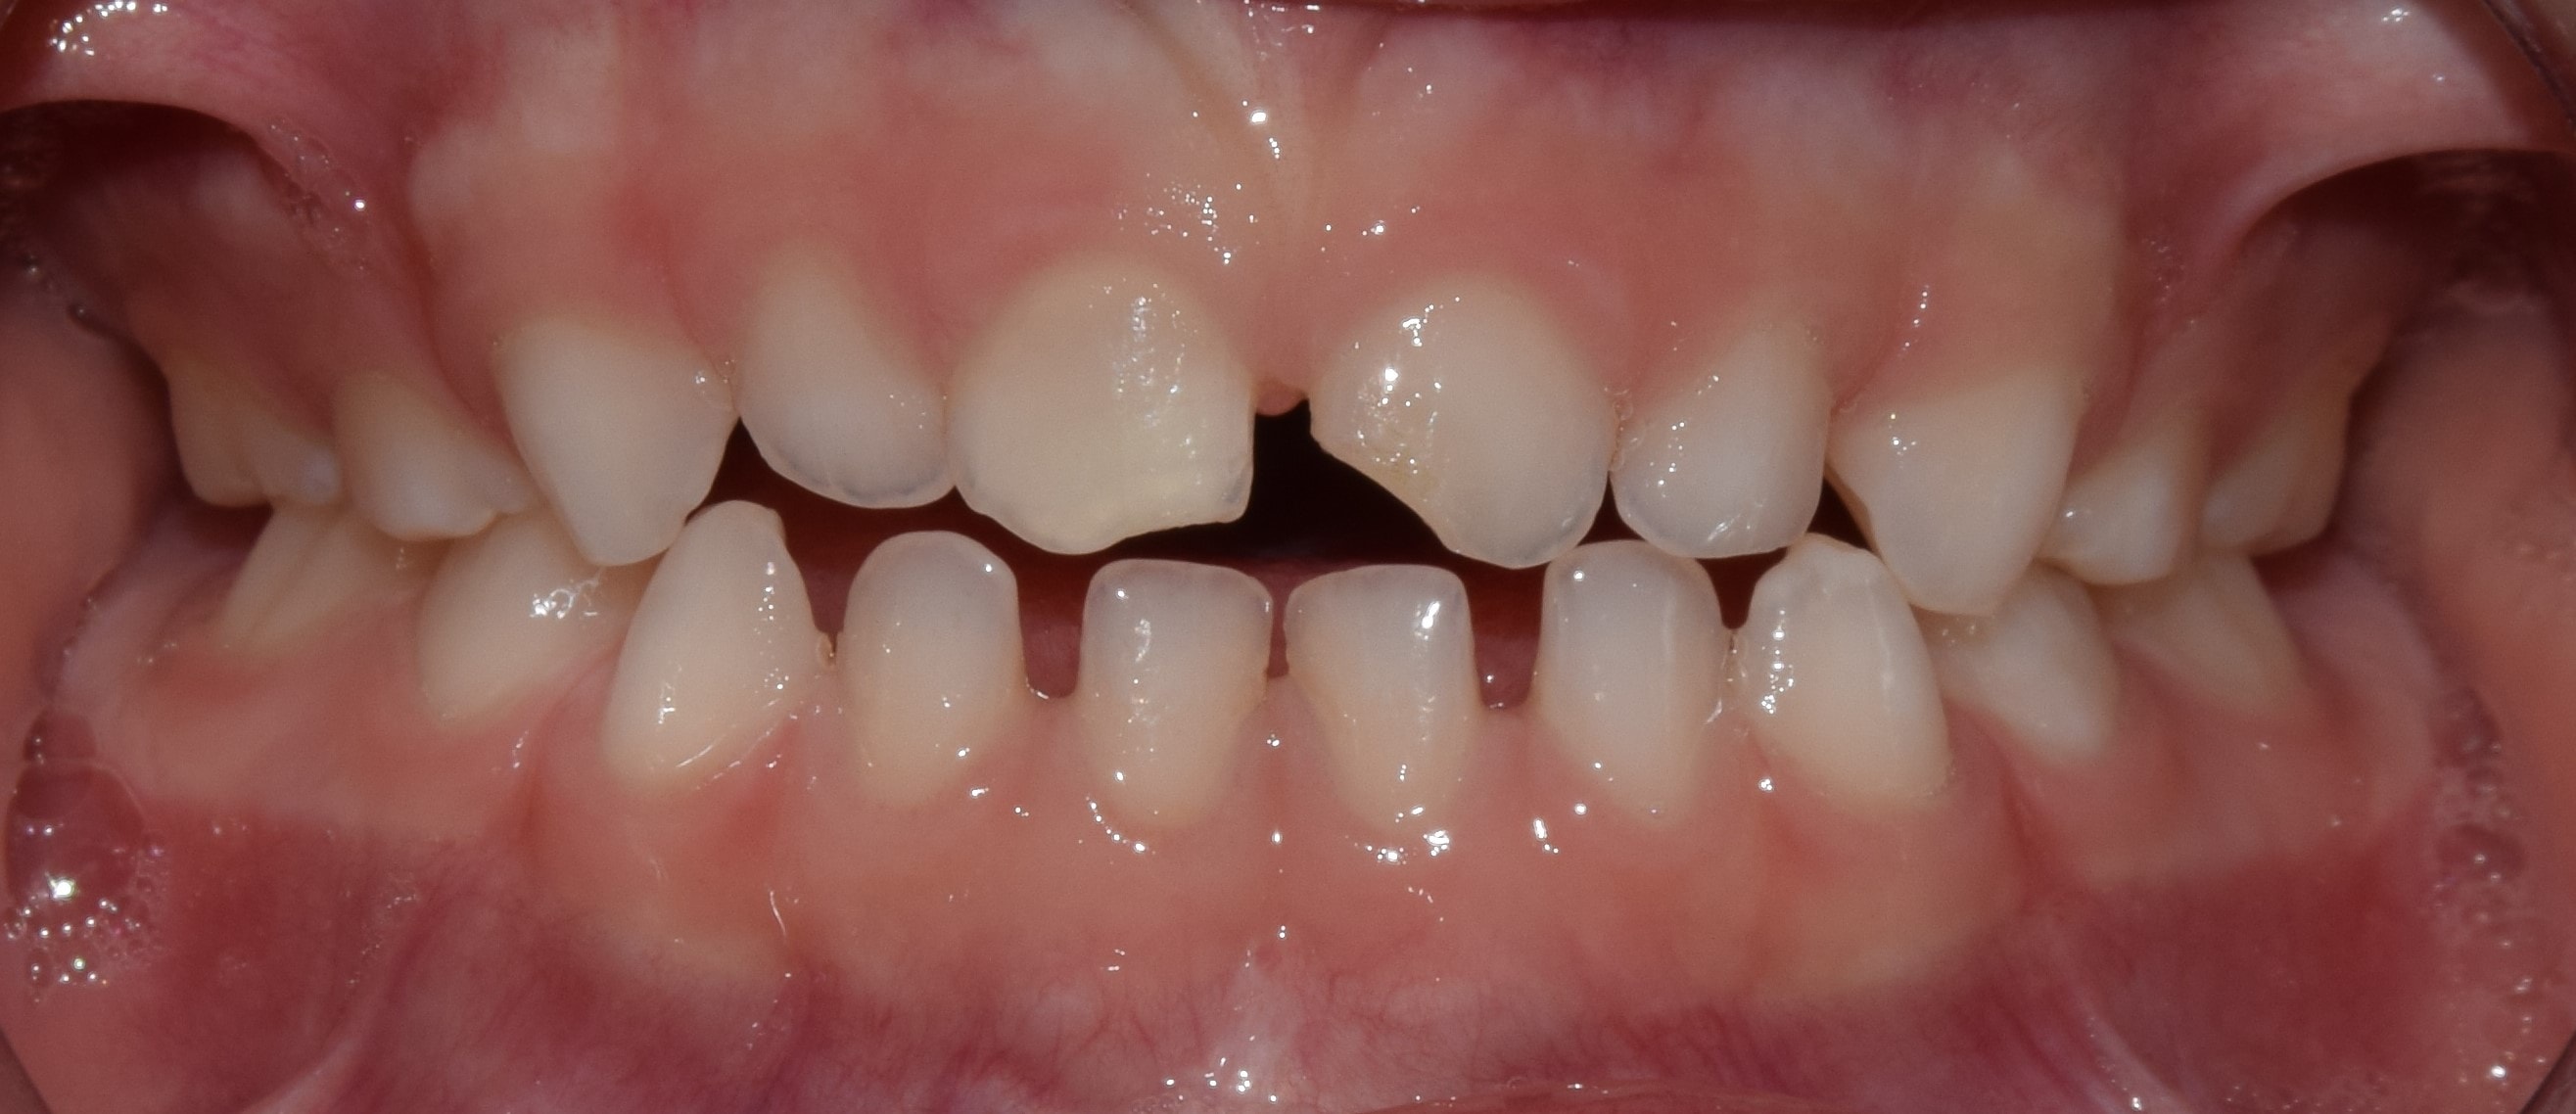

Diasthema medianum

Gyakori fogszabályozási probléma a két felső nagymetsző között jelentkező rés. Ellátását számos faktor befolyásolja. A vegyesfogazatban gyakori, legtöbbször normális jelenség, ami később spontán záródhat, ezért túlságosan korai ellátását semmi sem indokolja. Diasthemat eredményezhet például kifejezett ajakfék, számfeletti fog, kismetsző csírahiány.